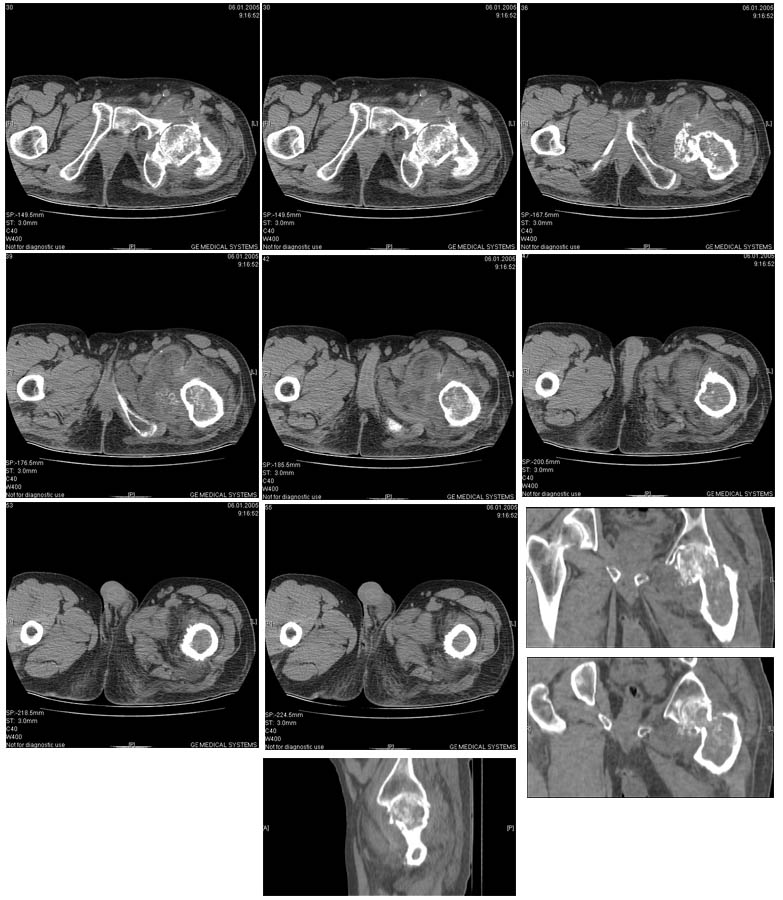

И снова вопрос по эндопротезированию: Пациенту 51 год. Болен с 2000 г, когда отметил умеренные, нараостающие боли в в/3 левого бедра, прогрессирующую контрактуру лев Т/Б сустава.

05.12.04 после падения на бедро боли резко усилились, нога стала неопорной. На рентгенограмме обнаружен патологический перелом шейки бедренной кости. Обследован в отделении костной онкологии. Результат биопсии: асептический некроз проксимального отдела бедренной кости. Вопрос: выбор технологии эндопротезирования - цементная или бесцементная версия. Заранее благодарю! С уважением,А.В.Владзимирский

Проксимальный отдел бедра не виден достаточно на представленных рентгенограммах; но то, что видно, как раз наводит на мысли о цементной фиксации - цилиндрический канал, измененный calcar, кистозные изменения в области большого вертела и т.д.

Как то очень подозрительно выглядит проксимальный отдел бедра для такого очень простого гистологического заключения. Вы уверены, что гистология настолько благополучна и в каком варианте она выполнялась: пункционная или открытая с забором костного блока? Не уверен на все сто , но область проксимального отдела бедра - одно из излюбленных мест для гигантоклеточной опухоли, которая зачастую озлакочествляется (имел два подобных наблюдения). Из своей практики могу сказать, что, к сожалению, информативность пункционной биопсии не сравнима с открытой техникой. Поэтому прежде чем решать цементный или бесцементный протез использовать, я бы повторил биопсию в сочетании со сканированием скелета, сывороточная щелочная фосфатаза, кальций, фосфор сыворотки, СОЭ, С- реактивный белок,

Soglasen s Евгений И Чекашкин, proximal Femur does not look right. Sarcoma? Pagets, Osteomyelitis?. Technicality of the implantaion will be dependent upon underlying pathology, and the surgeon's level of comfort.

Действительно, проксимальный отдел бедра выглядит подозрительно. По-моему напоминает болезнь Педжета. Кстати, гистологическое заключение в таком случае часто звучит как "хроническое воспаление", "асептический некроз с элементами лейкоцитарной инфильтрации" и т.п. Далеко не все патоморфологи имеют достаточный опыт для дифференцировки костной патологии.